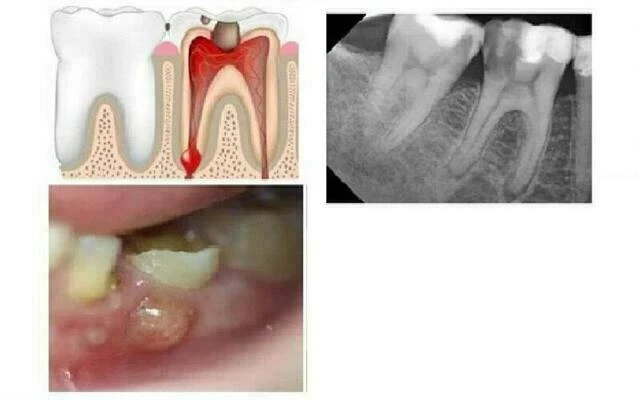

Áp xe quanh chóp cấp tính

Răng bị áp xe quanh chóp cấp tính sẽ đau dữ dội khi cắn, gõ hoặc lay răng. Răng không đáp ứng với bất kỳ thử nghiệm độ sống tuỷ nào và sẽ lung lay ở những mức độ khác nhau. Hình ảnh X quang biểu hiện sự giãn rộng của dây chằng nha chu cho đến thấu quang quanh chóp. Sưng trong miệng và mô ngoài mặt gần với răng bệnh lý với những mức độ khác nhau. Bệnh nhân thường sẽ bị sốt, các hạch bạch huyết cổ và dưới hàm sẽ nhạy cảm khi sờ nắn.

Áp xe quanh chóp mạn tính

Răng bị áp xe quanh chóp mạn tính thường sẽ không có triệu chứng lâm sàng. Răng sẽ không đáp ứng với thử nghiệm độ sống tuỷ và hình ảnh X quang sẽ biểu hiện thấu quang quanh chóp. Răng thường không nhạy cảm khi cắn nhưng có thể bệnh nhân sẽ “cảm thấy khác” khi gõ. Bệnh lý này có thể được phân biệt với viêm quanh chóp không triệu chứng vì nó có sự thoát mủ qua lỗ dò.